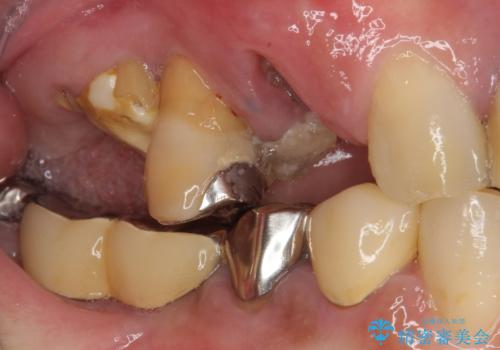

- 歯が破折しているため、抜歯が必要であると近医で診断されてからも放置を続けてしまったとのことで来院された患者様です。

臼歯はもはや咬み合わせに寄与していない状態であり、3歯を抜去してインプラント2本埋入によるブリッジ補綴を計画しました。